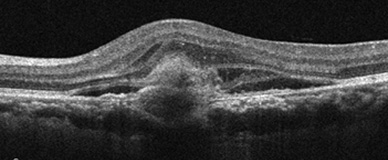

습성 황반변성

유리체내 주사모두다연세안과는 황반변성 진단에 최적화된 정밀 진단 장비와 숙련된 의료진, 맞춤형 치료 전략, 지속적인 사후 관리를 통해 환자분의 삶의 질을 높입니다.

건성과 습성 형태에 따라 최적의 치료 계획을 세우고, 정기 검진과 신속한 치료 연계를 통해 시력 보호에 최선을 다합니다.